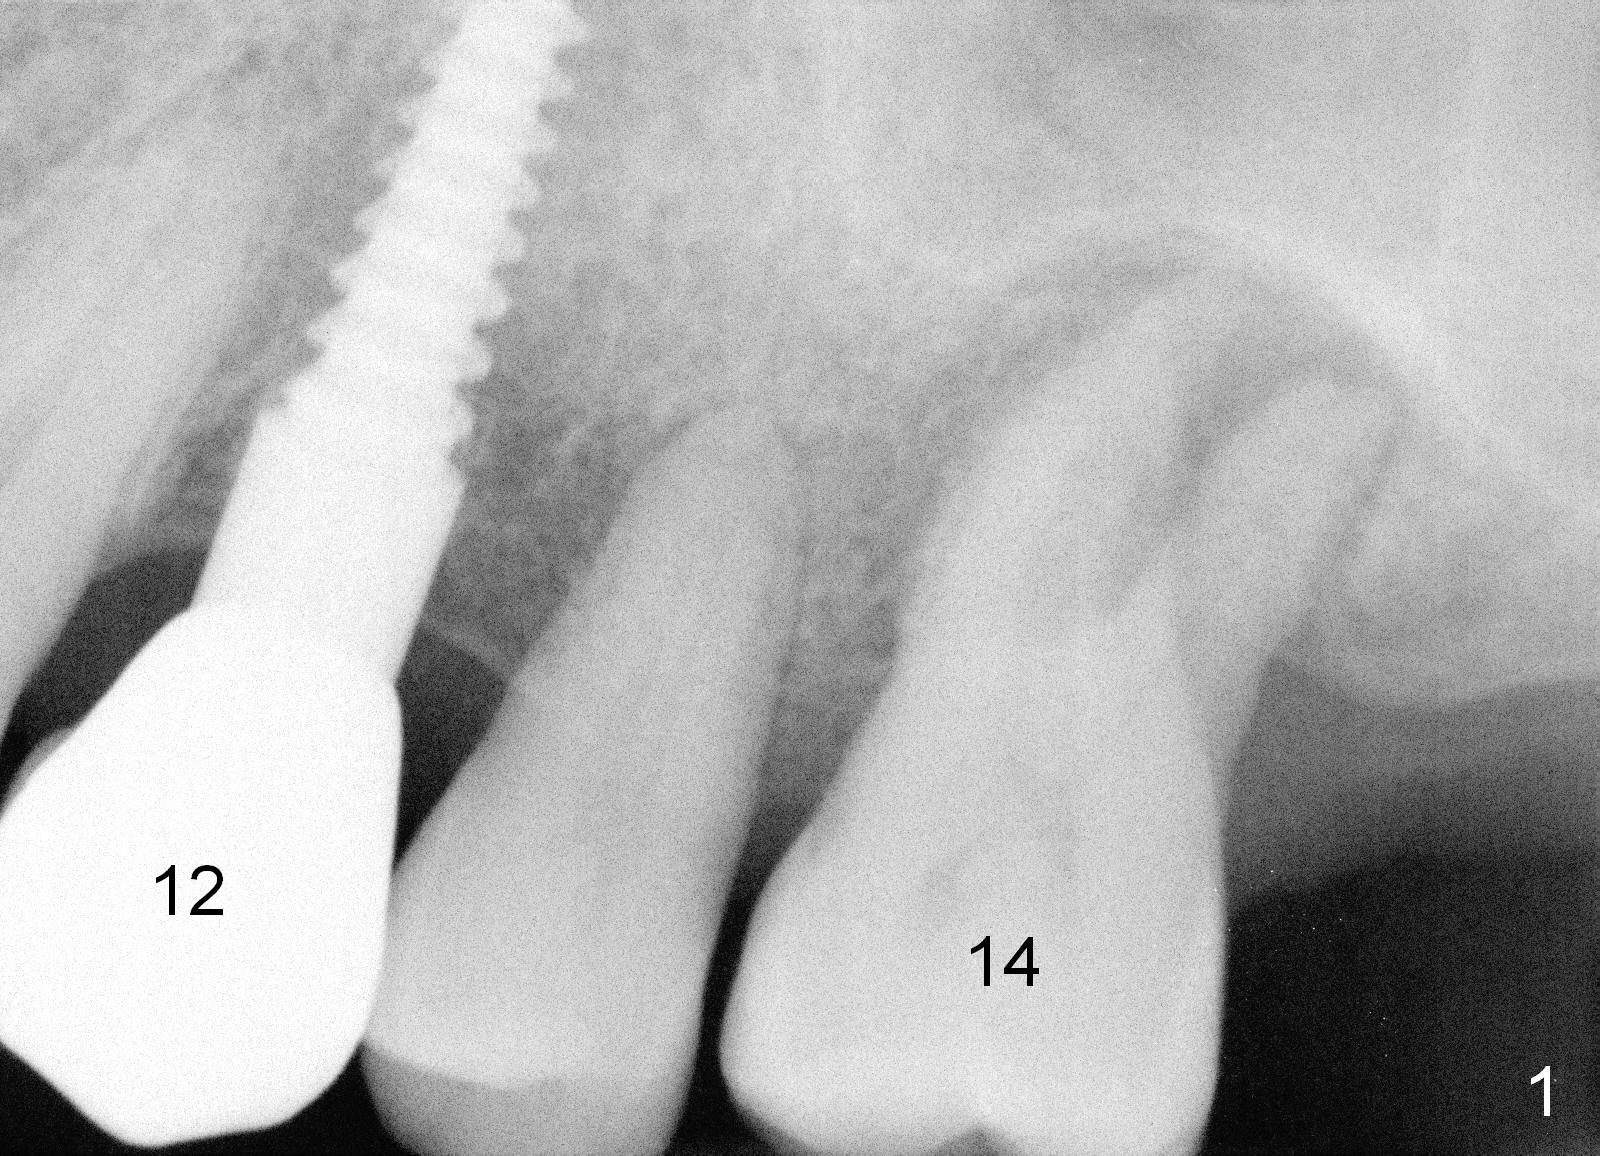

A 52-year-old man (DM) will return for #14 extraction and immediate implant nearly 2 years after #12 crown cementation. There is more bone loss distally than mesially. Clinically, the palatal recession is excessive (Fig.3). After socket debridement and 2% Xylocaine/1:50,000 Epinephrine gauze packing, osteotomy will be initiated in the buccomesial aspect of the septum, if the latter is present. Use 4.5 or 5x17 mm tap to test stability and more importantly determine how much thread exposure can occur palatally before placing a 14 or 17 mm long implant (Fig.2). A fair amount of bone graft will be inserted distopalatally (red circles in Fig.2). If primary stability is achieved, use an immediate provisional to close the socket opening.